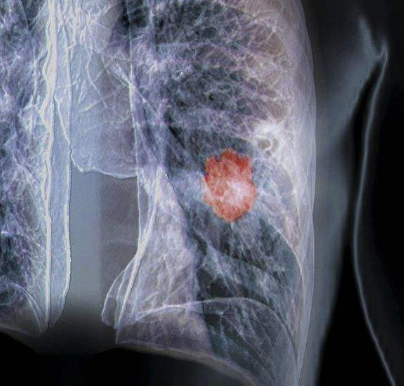

肺癌是發(fā)病率較高的惡性腫瘤,其惡性程度是很高的,肺癌在藥物化療時,會出現(xiàn)耐藥性,這是一個治療上的難題,較近,美國科學(xué)工作者,通過對表皮生長因子受體(EGFR)突變的非小細(xì)胞肺癌(NSCLC)患者進(jìn)行研究,鑒別出了一種特殊酶類與癌癥形成及對治療方法耐受性直接相關(guān),研究人員認(rèn)為,現(xiàn)有的兩種治療方法對這種致死性常見肺癌或許具有一定的治效果果,但這種肺癌常常會在患者治療一年內(nèi)發(fā)生復(fù)發(fā)。

研究者揭示了NSCLC腫瘤中所發(fā)現(xiàn)的名為PKCδ的蛋白激酶C和EGFR酪氨酸激酶抑制劑(TKIs)標(biāo)準(zhǔn)化治療方法之間的特殊關(guān)系,基于對小鼠和人類組織樣本進(jìn)行研究,這種關(guān)聯(lián)或許就能幫助PKCδ降低TKIs預(yù)防癌癥形成的能力。目前在美國每年大約會有16萬人會被診斷為NSCLC,而且大約有1.5萬人會出現(xiàn)攜帶EGFR突變的癌癥轉(zhuǎn)移疾病。

EGFR屬于受體酪氨酸激酶(RTKs)家族的蛋白,其常常會在NSCLC中發(fā)生頻繁突變,從而誘發(fā)細(xì)胞損傷,包括增強細(xì)胞生長、腫瘤形成和轉(zhuǎn)移等,TKIs能夠干擾EGFR的細(xì)胞信號并抑制腫瘤的發(fā)育;然而在治療腫瘤時較終會因多種機制讓腫瘤對治療方法產(chǎn)生耐受性,其中一種機制就是腫瘤的異質(zhì)性耐藥性,其包括EGFR的額外突變和其它RTKs的過量表達(dá)等。